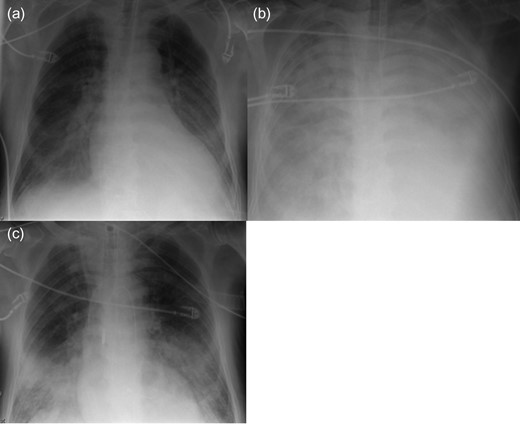

A 72-year-old man with a huge ventricular aneurysm due to a previous myocardial infarction in the anterior wall experienced an acute large myocardial infarction in the posterior wall due to total occlusion of the right coronary artery. Despite emergency coronary intervention at a regional hospital, his condition worsened and severe CS developed. After an emergency call, our ECLS team implanted ECLS percutaneously through the right femoral vessels, then the patient was transferred to our hospital. His condition rapidly stabilized. His left ventricular ejection fraction was ~20%, with a giant ventricular aneurysm on the anterior wall, akinesia of the posterior wall, and moderate mitral valve regurgitation (MR). On Day 7, chest radiography indicated that PE had worsened (Fig. 1a and b). Echocardiography revealed new onset of a small ventricular septum perforation that had not been detected by daily echocardiography. On Day 8, the Impella system was percutaneously implanted through the left femoral artery for direct unloading of the LV as therapy for PE. After Impella implantation, PE considerably improved (Fig. 1c). The flow from the Impella system was 2.0 l/min, whereas the flow from ECLS remained unchanged at 6 l/min; therefore, he had more output than before Impella implantation. However, his general condition had worsened due to sepsis and he died 2 days after Impella implantation.

Radiography of Patient 1. (a) After ECLS implantation. (b) Before Impella implantation. (c) Two days after Impella implantation.